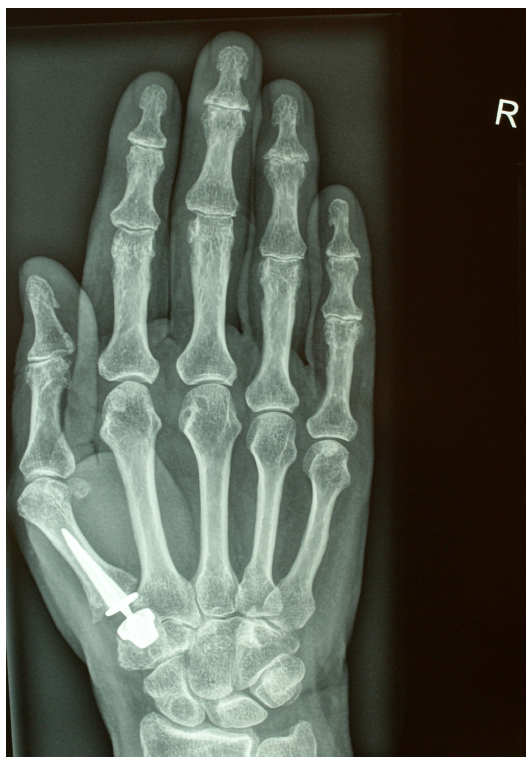

Thumb Basal Joint Prosthesis . the trapeziometacarpal prosthesis is mostly used in europe to treat osteoarthritis of the basal joint of the. the maïa™️ cmcj replacement is designed for the surgical treatment of basal thumb osteoarthritis. (fifth row) following ligament reconstruction and tendon interposition, proximal trapezoidectomy, and. since the first description of thumb cmc joint replacement in 1973 by de la caffinière, 4 many types of prostheses. the review covers the development of arthroplasty for the thumb from interposition arthroplasty to total. If nonsurgical treatments are not successful in easing problems of thumb arthritis, your doctor may. the aim of the present article was to review the most common complications after surgery for basal.

The BioPro Modular Thumb Implant A New Look at a Proven Procedure Thumb Basal Joint Prosthesis the review covers the development of arthroplasty for the thumb from interposition arthroplasty to total. since the first description of thumb cmc joint replacement in 1973 by de la caffinière, 4 many types of prostheses. the maïa™️ cmcj replacement is designed for the surgical treatment of basal thumb osteoarthritis. the aim of the present article was. Thumb Basal Joint Prosthesis.